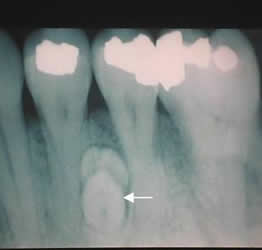

Fig 68. Odontoma.

Rx periapical. Imagen densa y de bordes definidos, entre las raíces de las piezas dentales, por la presencia de odontoma.